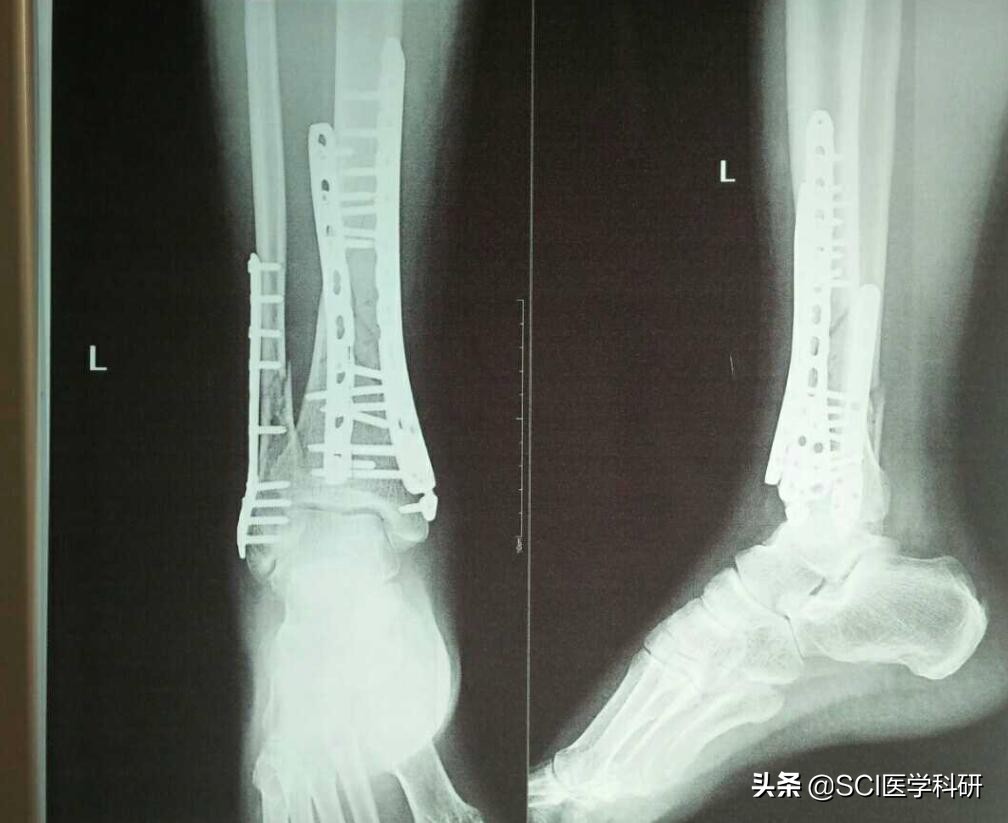

骨折的类型

儿童骨折还容易出现3种特殊类型,即青枝骨折、骨膜下骨折和骨骺损伤。

青枝骨折骨折时就像新鲜嫩枝,一侧骨皮质及骨膜断裂,另一侧完整,形成弯曲畸形。

骨膜下骨折为完全性骨折,但因骨膜厚,骨头仍保持完整而无移位。

骨骺损伤长骨两端膨大部分称为骨骺,儿童的四肢长骨干骺端与骨骺之间有一盘状软骨结构,称为骺板。骨骺和骺板都是末成熟的四肢长骨的生长区域,也是儿童骨骼的最薄弱和最易骨折的部位。如果骨骺受损而未及时发现和得到正确有效的处理,极易造成骨折畸形愈合及日后渐进性生长畸形,导致不可挽回的严重后果。